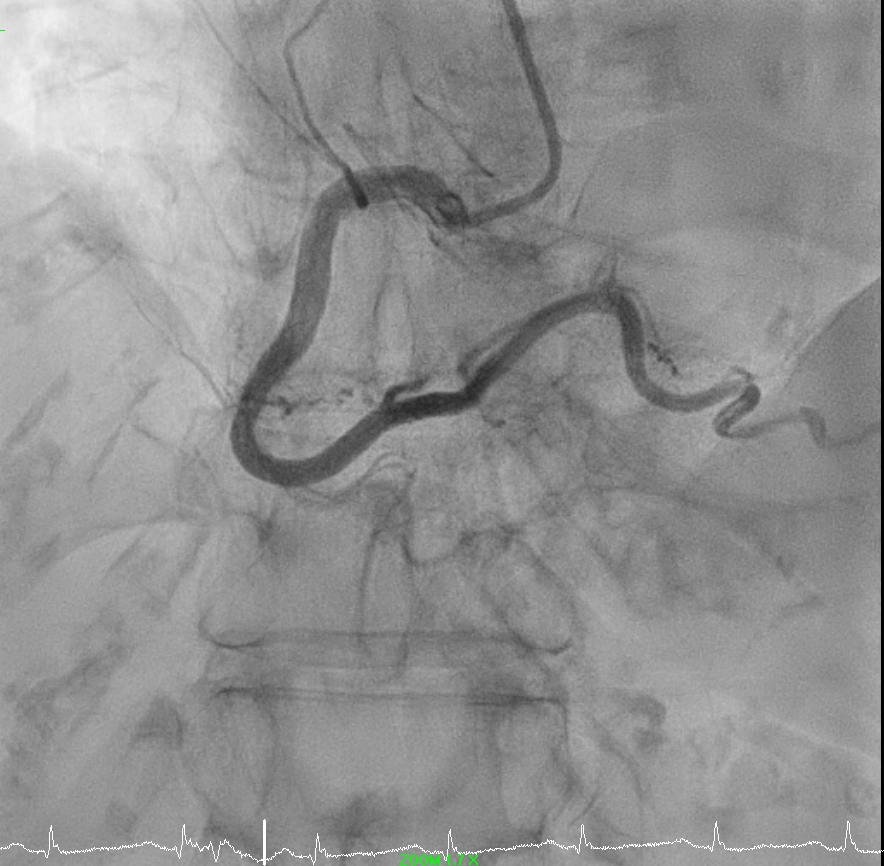

While attempting to engage right coronary artery, noted loss of pressure.

Catheter kinked in a figure of 8 position around left subclavian area.

Attempted to unkink by untwisting with 0.035" J tip guidewire support of failed.

Kinked part of catheter brought down to left arm area and attempted to unkink with inflated cuff and compression was not successful as well.

Right femoral puncture and Snare Amplatz Goose Neck 20mm advanced to distal tip of catheter.

Distal tip of catheter was snared and manage to unkink catheter.

Optitorque 5FR catheter successfully removed from left radial sheath.

Right femoral closed with Perclose Prostyle 6FR.